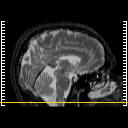

MR Study #5, March 10, 1991 -- Slice #2

[Home][Help][Clinical][Tour 1][Tour 2] Slice 2

Click on sagittal image to select slice. Click on thin tickmark to change timepoint, or thick tickmark for overlay.